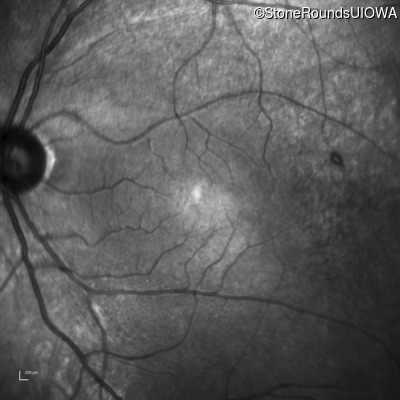

Infrared Fundus Photograph - Right - 20/20 -1

Exemplar

Infrared Fundus Photograph - Left - 20/30 +2